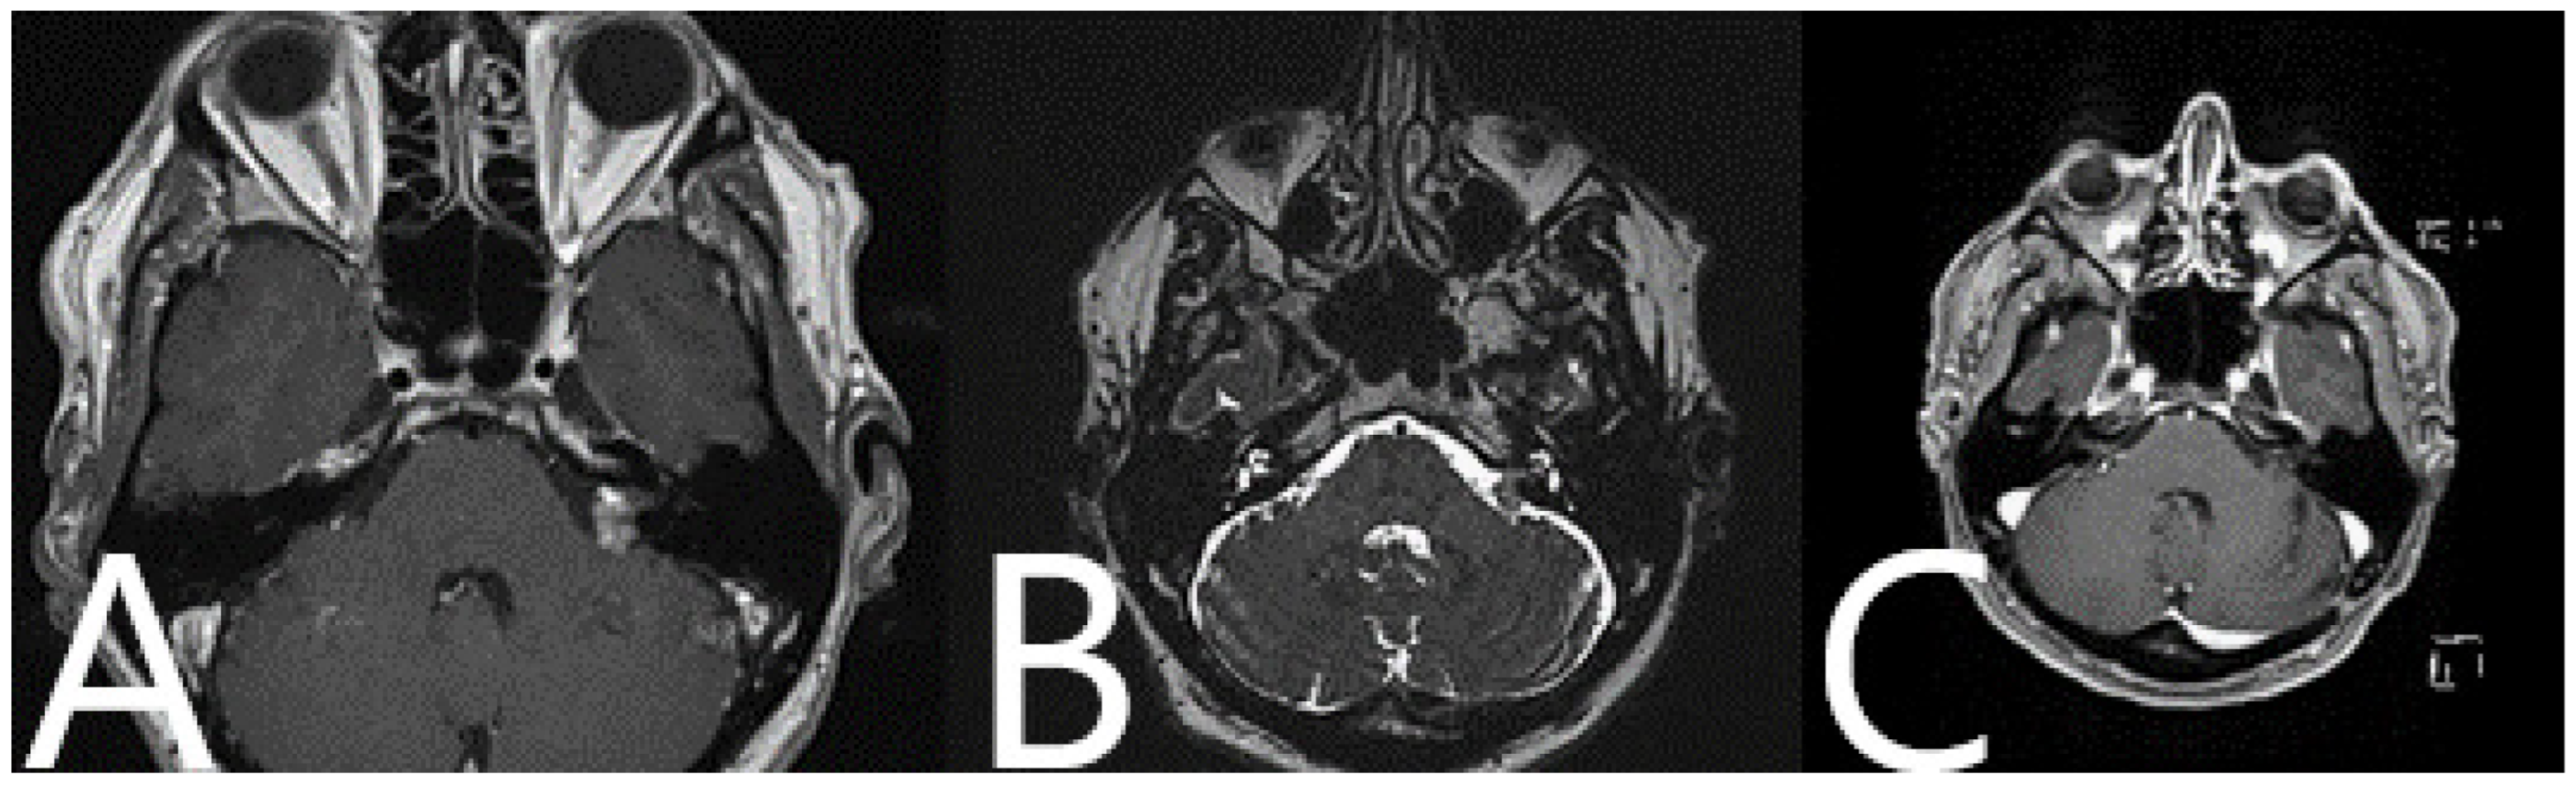

Illustrative Cases